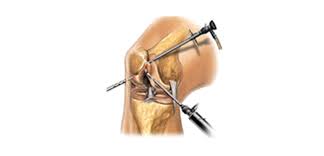

가장 중요한 것은 우리가 왜? 아픈가? 근본적인 원인을 파악하고 치료 계획을 하는 것이 중요하다. 영양제로 충분히 호전이 가능한가? 아니면 병원으로 가서 진단을 받고 어떤 것인지 선택 해야 된다.

지금 현재 나와있는 콘드로이틴 설페이트는 관절 건강을 위해 관절 통증, 염증을 줄이기 위해 글루코사민과 함께 자주 복용되는 건강기능식품 영양제로 알려져 있다. 몇몇 연구로 통해 콘트로이틴 황산염 영양제가 관절 통증과 기능면에 긍정적이 효과를 보인다고 발표한 바가 있다.

✅또한 콘드리이틴 설페이트는 연골에서 발견되는 자연적으로 발생하는 화학물 염증을 줄이고, 관절의 유연성과 운동성을 도와주는 역할을 하고 있다.